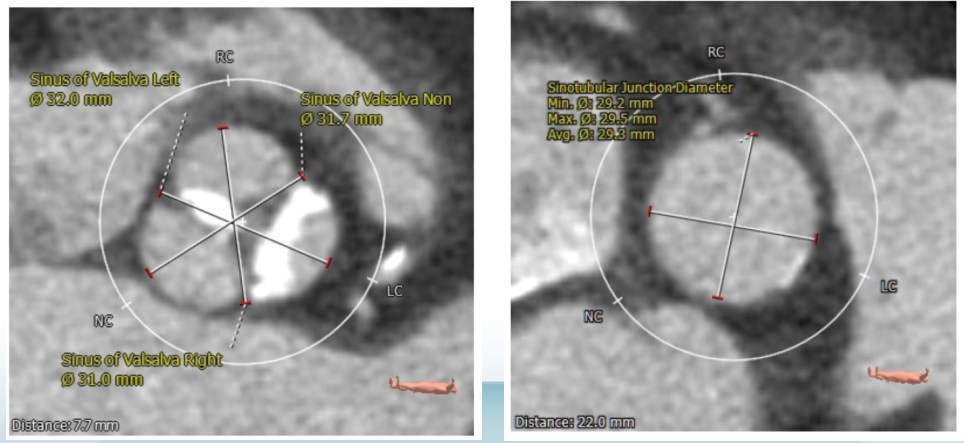

术前CT评估-主动脉窦及STJ

术前CT评估-冠脉开口高度